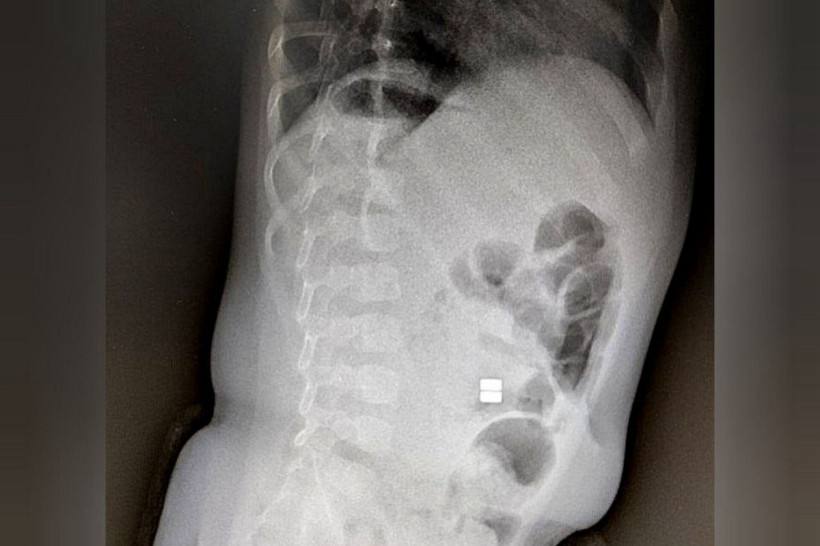

Поводом стали участившиеся случаи, когда малыши проглатывают магнитные шарики из конструктора. Подобные ситуации зачастую влекут за собой необратимые последствия для здоровья. И очень хорошо, если ребенок вовремя попадет на операционный стол.

Главная опасность в подобных историях кроется в том, что диагностика крайне затруднительна. Если родители по каким-то причинам не указывают на факт проглатывания несъедобных предметов, то постановка диагноза будет запоздалой!